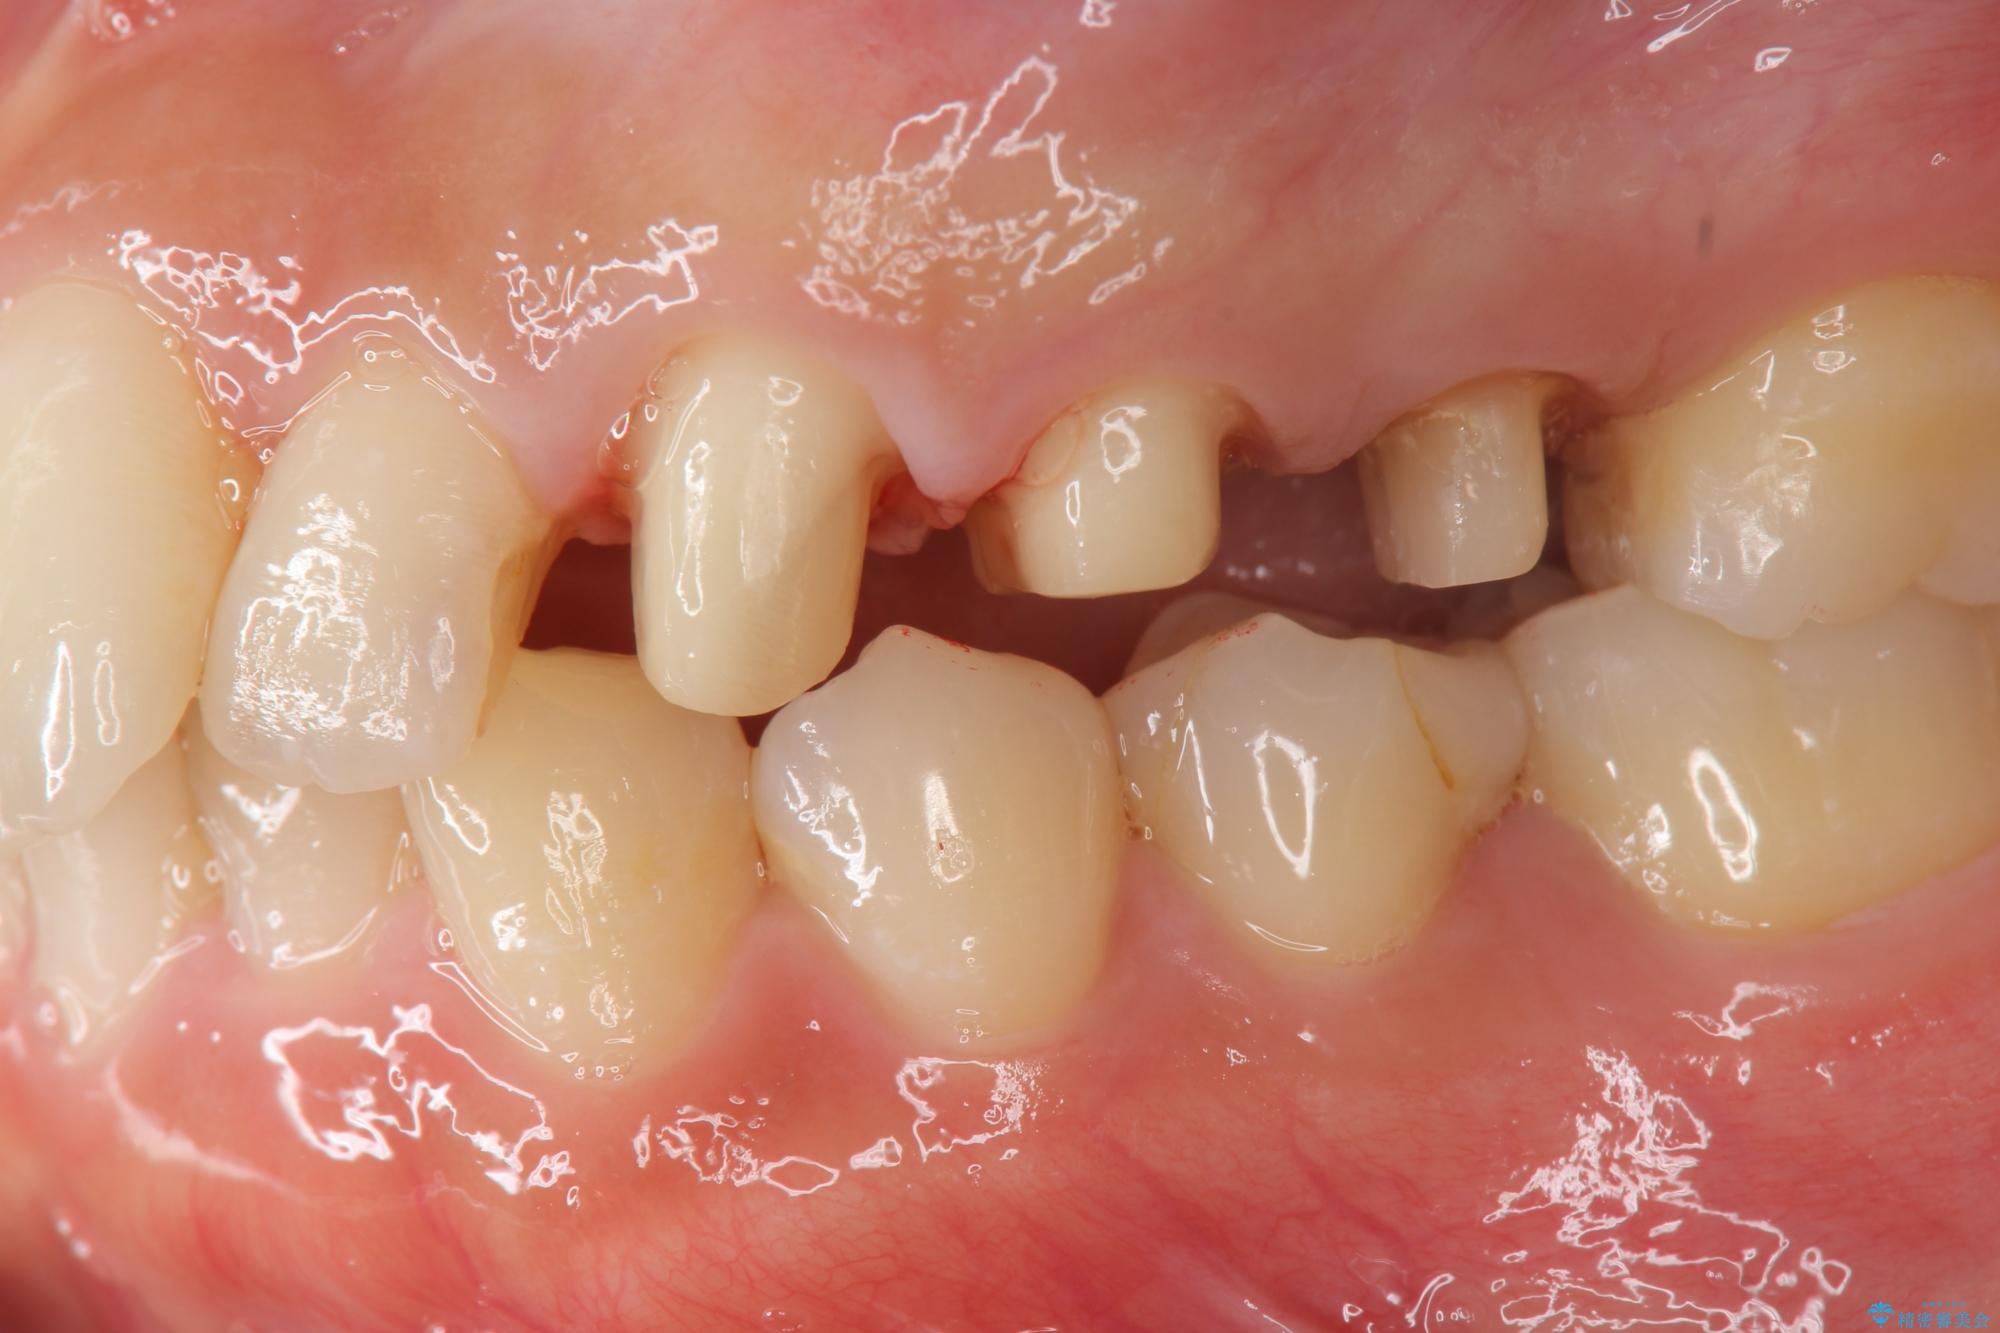

歯の水平・垂直的位置を整備したセラミッククラウン治療

当初、歯ぐきよりも深い虫歯のぞんざいや、歯のポジションに問題がありましたがマルチブラケットを用いた部分矯正を行うことで適切な位置へと歯を移動させ、歯周環境を整えたセラミック治療を行うことができました。